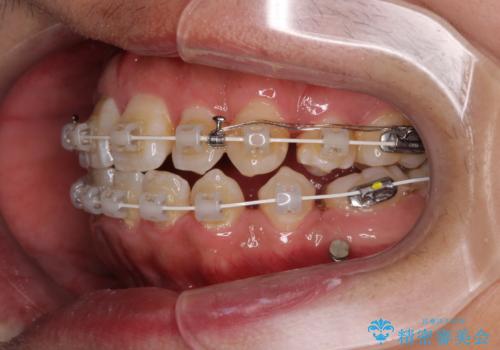

上下左右の小臼歯を抜歯し、歯列を整えるためのスペースを確保

左下は第二小臼歯に根管治療歴があったため、左下のみ第二小臼歯を抜歯しアンカースクリューを併用

それ以外の部位は第一小臼歯を抜歯

矯正中の見た目を気にされていたため、プラスチックブラケット+コーティングワイヤーを使用した、目立ちにくい審美矯正装置を選択しました。